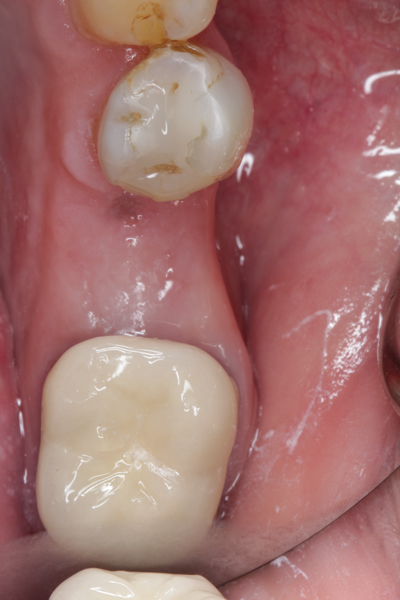

Fig 23. Implant inserted in a regenerated ridge after 6 months healing.

Figure 23

Fig 24. Cone beam scan demonstrating bone circumferentially around the dental implant.

Figure 24

Fig 25. Radiograph showing appearance of restored implant after 1 year.

Figure 25